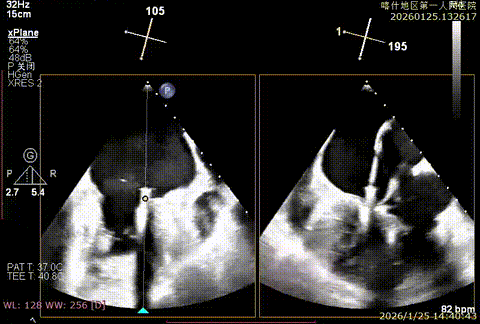

该例患者为DMR,1,2,3区均见脱垂,主要脱垂位于1区及外交界后叶脱垂,病变解剖结构亦相对复杂。术前制定手术策略:使用3把XTR解决患者瓣叶脱垂与二尖瓣反流。术中首先进行房间隔穿刺,最终穿刺高度4.5cm。穿刺成功后将SGC和XTR-CDS依次送入左心房,通过操控“M”旋钮调节SGC,使二尖瓣夹避开华法林脊并成功定位于2区正上方。在2区进行弹道测试成功后,进行Orientation调整。最终在1区将二尖瓣夹送入左心室,成功捕捞和夹持瓣叶后缓慢关紧夹。第二枚XTR植入2区,采用双拉链技术,从两个夹子中间植入第三枚夹子,固定脱垂区域降低反流。TEE检查见二尖瓣反流程度降低至少量,二尖瓣双孔组织桥稳定,肺静脉逆流改善明显,手术安全结束。

bicomm切面-大脱垂

X-plan 1区后叶脱垂

3D enface脱垂情况

X-plan 反流情况